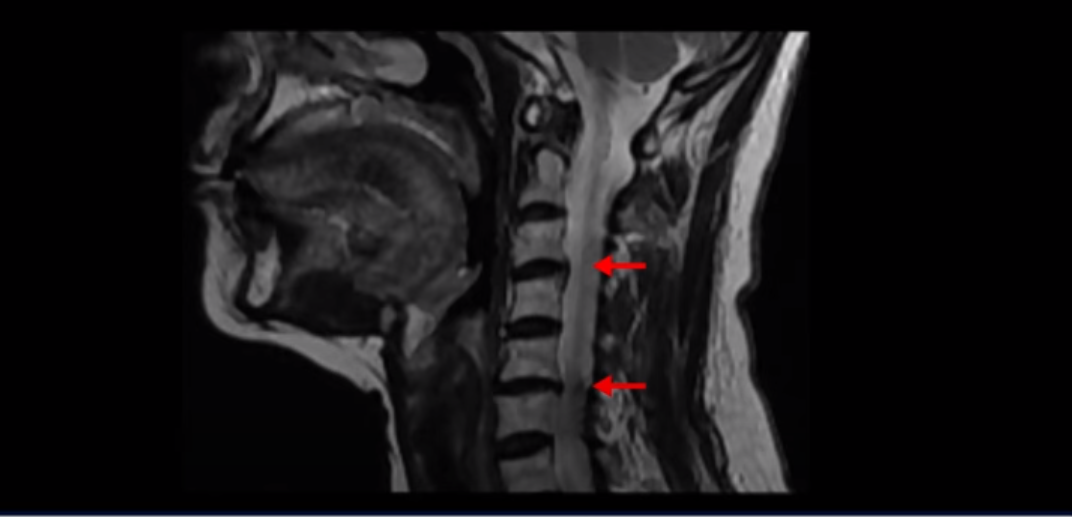

이 환자분은 원인을 알 수 없는 두통, 어지럼증, 메스꺼움, 눈 통증, 눈 침침함, 이명, 팔 통증 팔힘빠짐, 안면 감각 이상과 함께 극심한 목 통증과 어깨통증, 견갑골 통증을 3년 이상 겪으셨습니다. 이런 복합 증상들은 거북목으로 인해 목 근육, 특히 목 앞쪽 근육이 극심하게 뭉칠 때 나타나는 증상입니다. 이런 여러 가지 증상이 나타나는 이유는 거북목으로 인해 극심한 목 근육 뭉침, 특히 목 앞쪽 근육의 단축과 뭉침이 지속되면 목 근육 사이를 통과하는 목 주변의 혈관과 신경에 큰 영향을 미치기 때문입니다. 이 환자분은 고개를 숙이면서 하는 일을 오래하셨고, 그런 이유로 거북목으로 인한 목 앞쪽 근육 및 목 뒤쪽 근육 뭉침 모두 매우 심한 상태였습니다.

일반적으로 환자분들이 어지럽고 두통도 있고 하면 보통 이비인후과나 신경과에 많이들 가시는데, 목 문제 때문에 아픈 사람들은 당연히 이비인후과에서는 이상이 없다는 얘기를 듣고 또 신경과에서도 아무 이상이 없다고 듣거나 혹은 후두신경통을 진단받는 경우가 많습니다. 또 만성적으로 목과 어깨 근육이 뭉치면서 목 통증, 어깨통증이 있기 때문에 정형외과나 통증의학과, 한의원 등에 가면 근막통증증후군 같은 진단을 받는 경우도 많습니다. 게다가 이렇게 목이 아픈 환자분들은 척추병원에 가서 MRI를 찍어보면 이 환자분처럼 40세가 넘은 분들은 퇴행성 목디스크가 보이는 경우가 매우 많습니다.

이 환자분도 역시 이렇게 목디스크가 보이기 때문에 척추병원에서 목디스크 때문이라는 얘기를 듣고 신경 주사를 여러 번 맞게 되지만 목디스크 때문에 아픈 게 아니기 때문에 목디스크를 계속 치료해봐야 좋아지지 않는 겁니다.

이 환자분 역시 이비인후과, 통증의학과, 정형외과, 신경외과, 한의원 등 수많은 병원을 다 방문해 봤지만, 목디스크라는 얘기와 근육이 뭉쳐있다는 얘기만 듣고 신경 주사도 맞고 침 치료도 해봤지만 3년 동안 전혀 좋아지지 않았습니다. 왜 그럴까요? 앞에서 목 앞쪽 근육이 제일 큰 문제라고 말씀 드렸습니다.